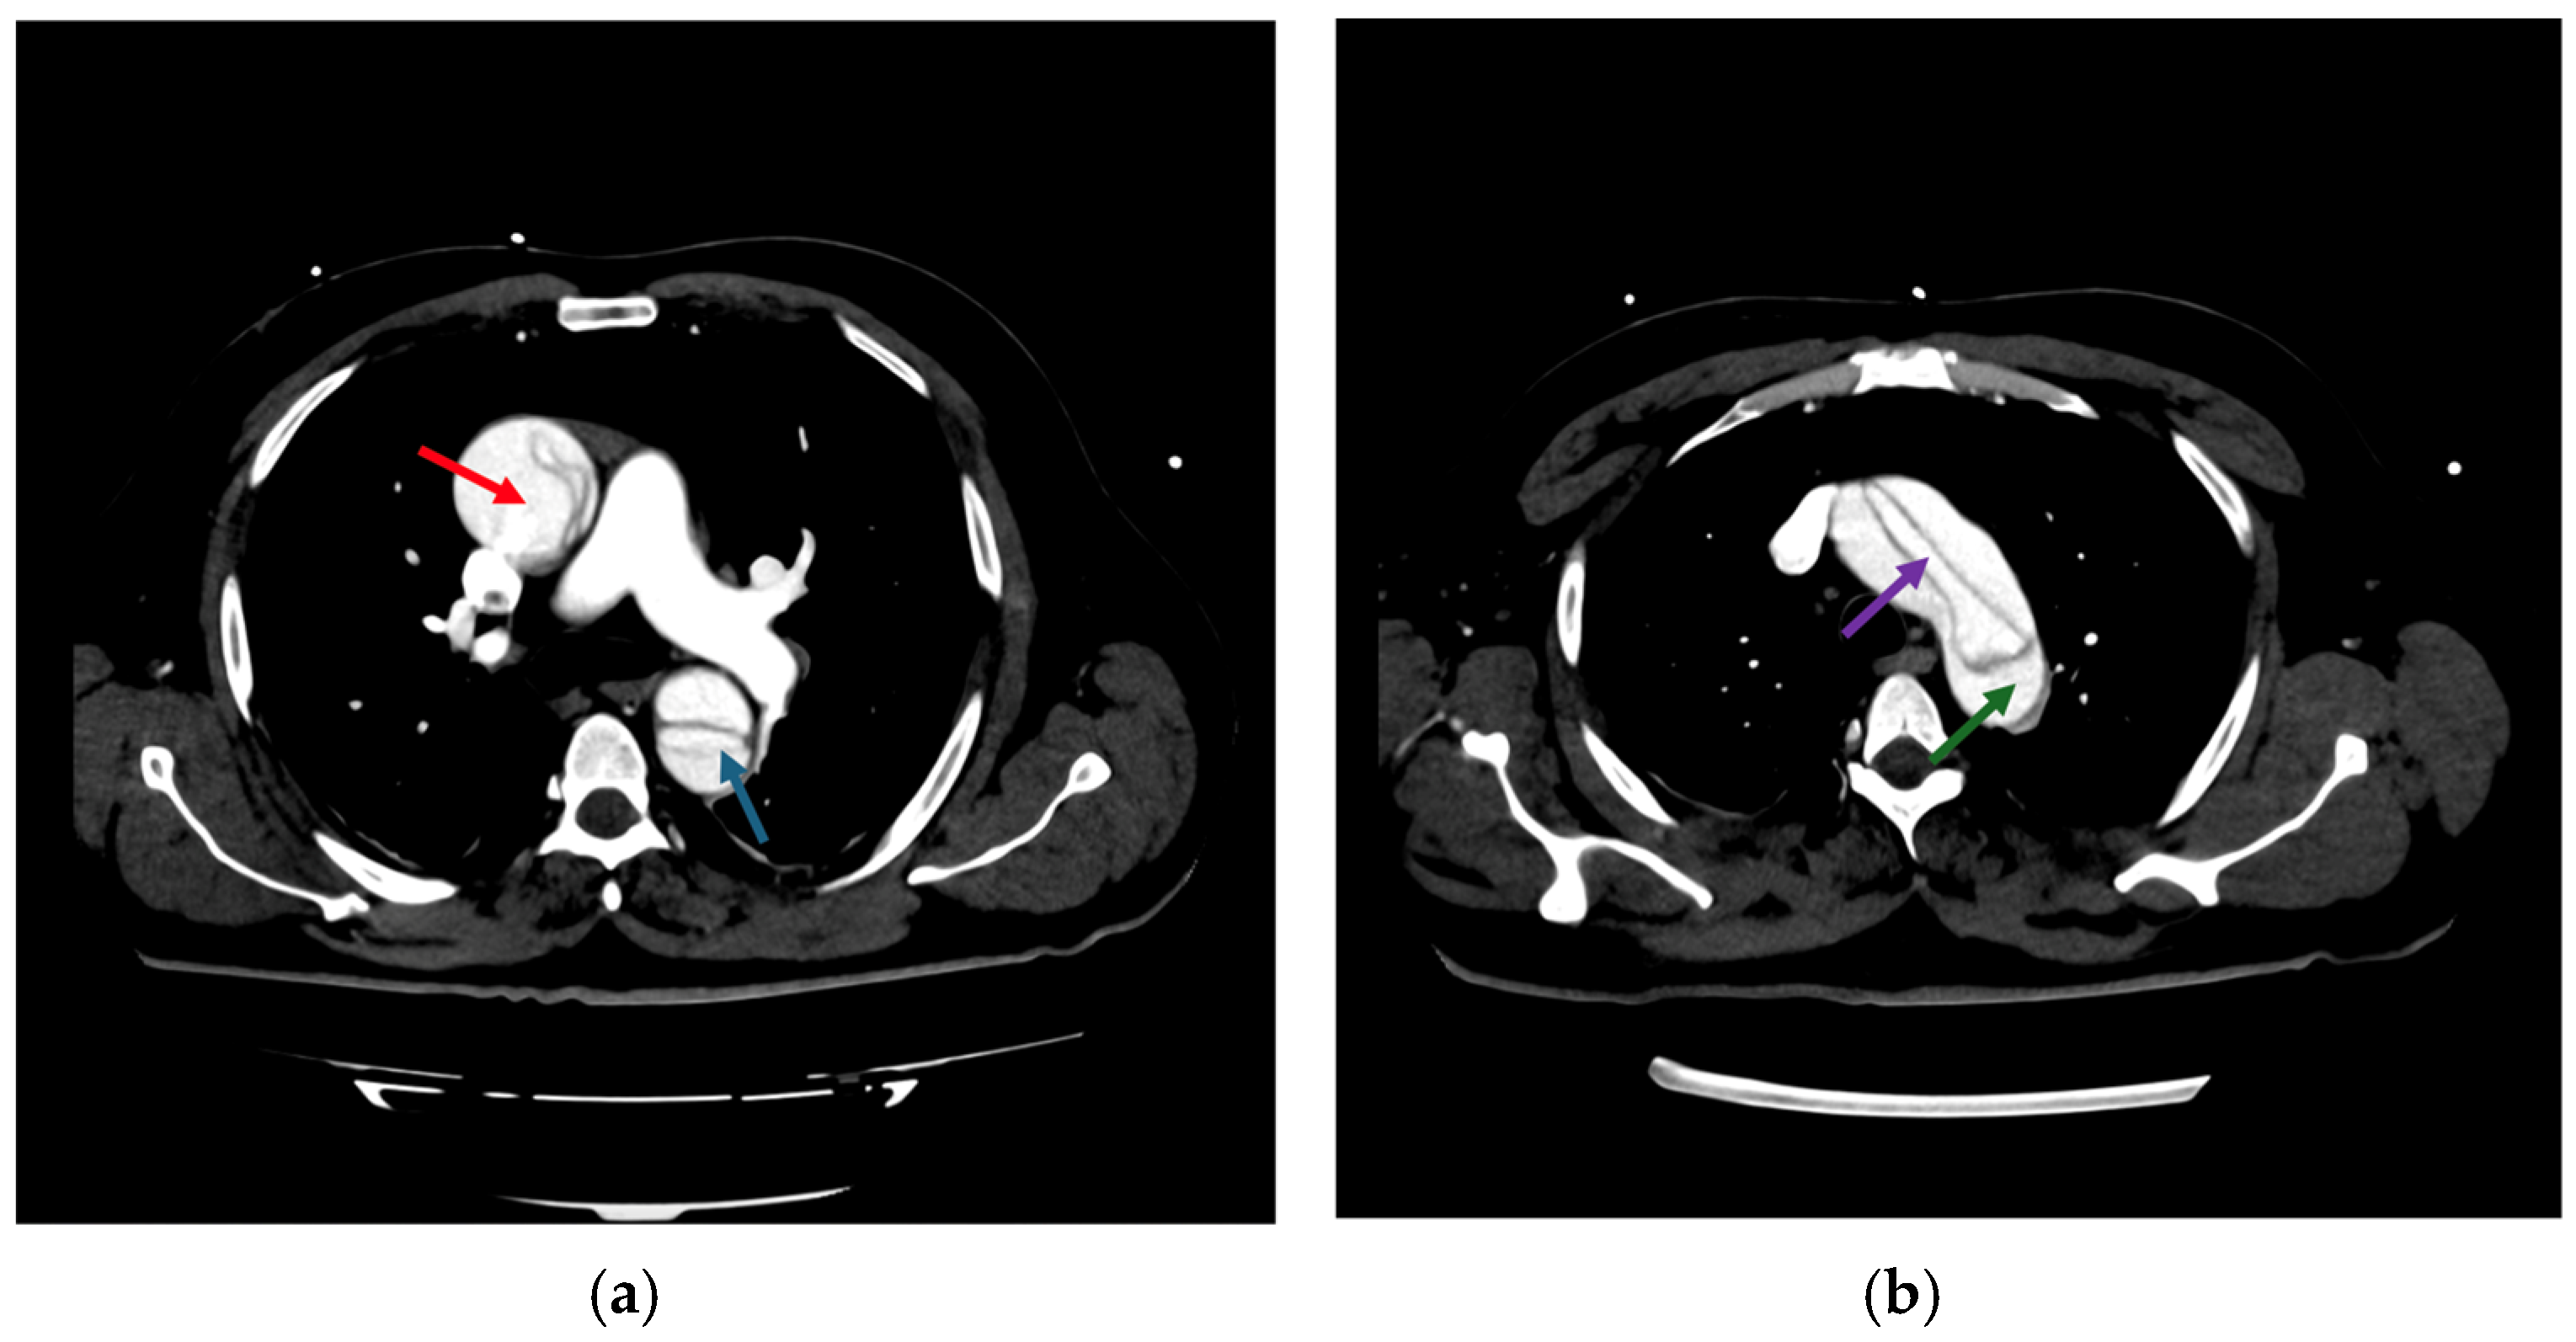

Imaging modalities, especially CTA, were essential for diagnostic and anatomical assessment. In our cohort, CTA findings directly influenced the management pathway in multiple instances. For example, in four cases (15.4%), pericardial effusion detected on imaging necessitated immediate surgical intervention to prevent cardiac tamponade. In nine patients (34.6%), extensive aortic arch involvement observed on CTA dictated the need for total arch replacement. Additionally, imaging findings identified branch vessel involvement in six patients (23.1%), which prompted closer intraoperative vascular assessment to prevent ischemic complications. These findings demonstrate that imaging was not merely a diagnostic tool but also a cornerstone in therapeutic decision-making, shaping both the urgency and extent of surgical intervention. This was exemplified by a representative case of a 57-year-old male with a complex DeBakey Type I dissection (Figure 9 and Figure 10). The case underscores the critical role of advanced imaging in identifying the extent of dissection and guiding timely surgical intervention, which is consistent with our study findings. The detection of aortic regurgitation in 26.9% and pericardial effusion in 19.2% underscores the efficacy of multimodal imaging in identifying problems that require immediate surgical intervention. Outcomes of surgical versus conservative management in our sample reflect findings from IRAD and other registries, revealing in-hospital mortality rates of 12.5% for surgically treated patients compared to 60.0% for those receiving conservative management. The decision between surgical and conservative management was primarily driven by patient stability, comorbidities, and imaging findings. Hemodynamic instability, evidence of rupture, and significant pericardial effusion were immediate surgical indications observed in 61.5% of our cohort. Conversely, conservative management was chosen in patients with advanced age, significant comorbidities, or family refusal of surgical intervention. Despite efforts to stabilize conservatively managed patients with pharmacological blood pressure control and vigilant monitoring, outcomes remained significantly inferior, highlighting the limitations of non-surgical approaches in Stanford Type A dissections. Kaplan–Meier survival studies indicated an 87.5% one-year survival rate for surgical cases against 30% for conservative care, highlighting the critical life-saving effect of prompt surgical intervention [20,21].

Figure 10. CT imaging of Stanford Type A aortic dissection: true and false lumen analysis—transverse sections: (a) compression of the true lumen (purple arrow) by the false lumen (green arrow) within the ascending aorta indicates compromised blood flow, necessitating immediate surgical intervention to restore adequate perfusion; (b) involvement of the descending thoracic aorta shows significant expansion of the false lumen (red arrow), with partial thrombosis and dynamic obstruction impacting distal perfusion (blue arrow). These findings underscored the urgency of surgical repair to prevent ischemic complications.